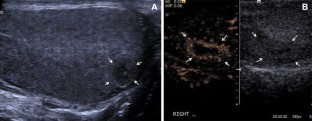

Fig. 2